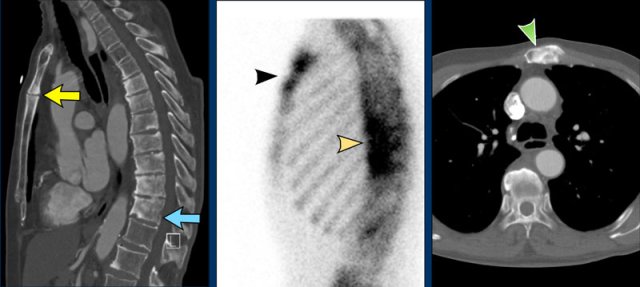

Patient with SAPHO syndrome with:

• osteïtis of corpus and manubrium sterni and sclerotic thoracic vertebral bodies, some endplate erosions and paravertebral syndesmophyte formation (left, sag CT)

• increased bone turonver (middle, bone scintigraphy)

• sclerosis in manubrium sterni (right, axial CT)